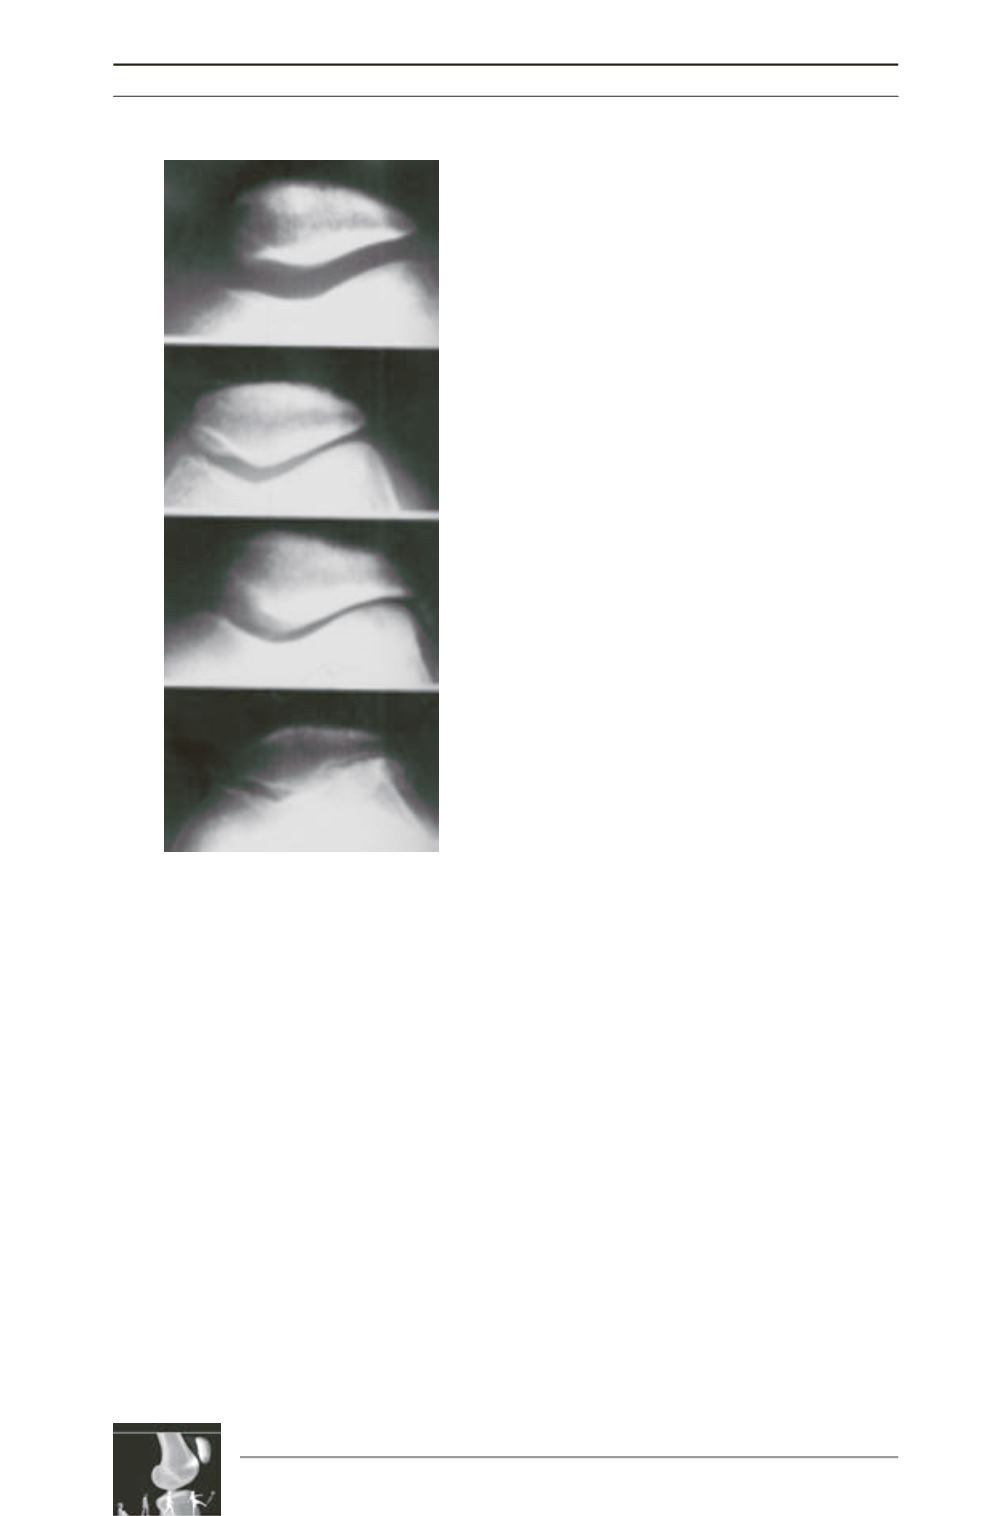

Fig. 1: Iwano classification

(source :

traité de chirurgie du genou, Ph. Neyret,

G. Demey, E. Servien, S. Lustig).